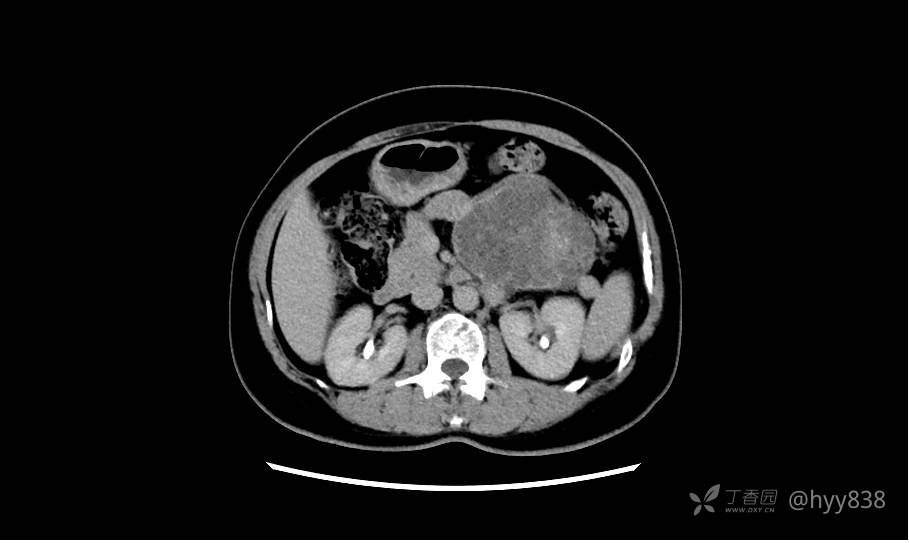

胰腺增强动脉期